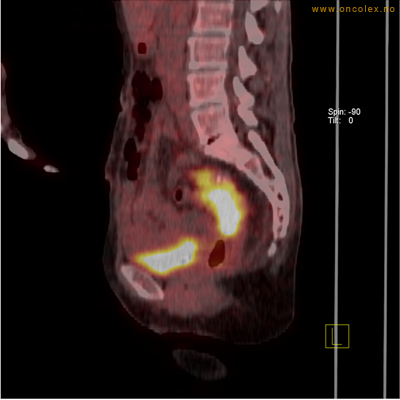

Eksempler på funn

Vev som tar opp mer radioaktivt stoff, synes som hvite områder som lyser opp mer i forhold til annet vev som tar opp mindre sukker.